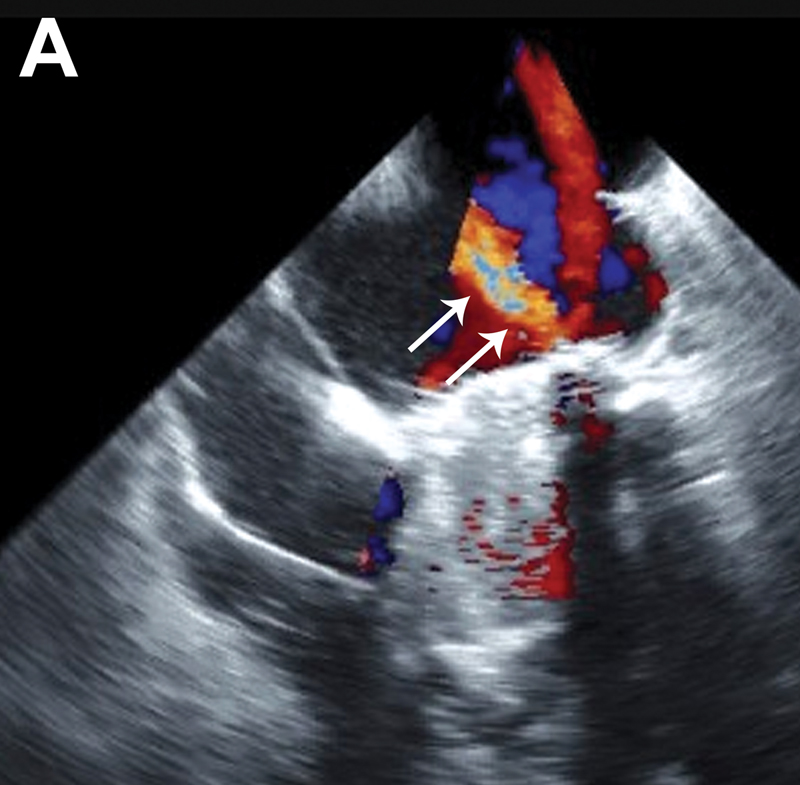

فحوصات تشخيصية لبعض امراض القلب والشرايين التاجية